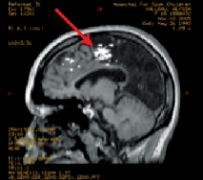

脑干海绵状血管瘤引起的脑干出血需要手术吗?海绵状血管瘤是指长在脑内的血管畸形,其中脑干部位的海绵状血管瘤是预后较差的颅内海绵状血管瘤,手...

脑海绵状血管瘤和癫痫发作:病灶切除术还是癫痫手术?海绵状血管瘤(CMs)是一种越来越被公认的部分性癫痫的原因。这些良性的桑葚样血管病变可能发生...